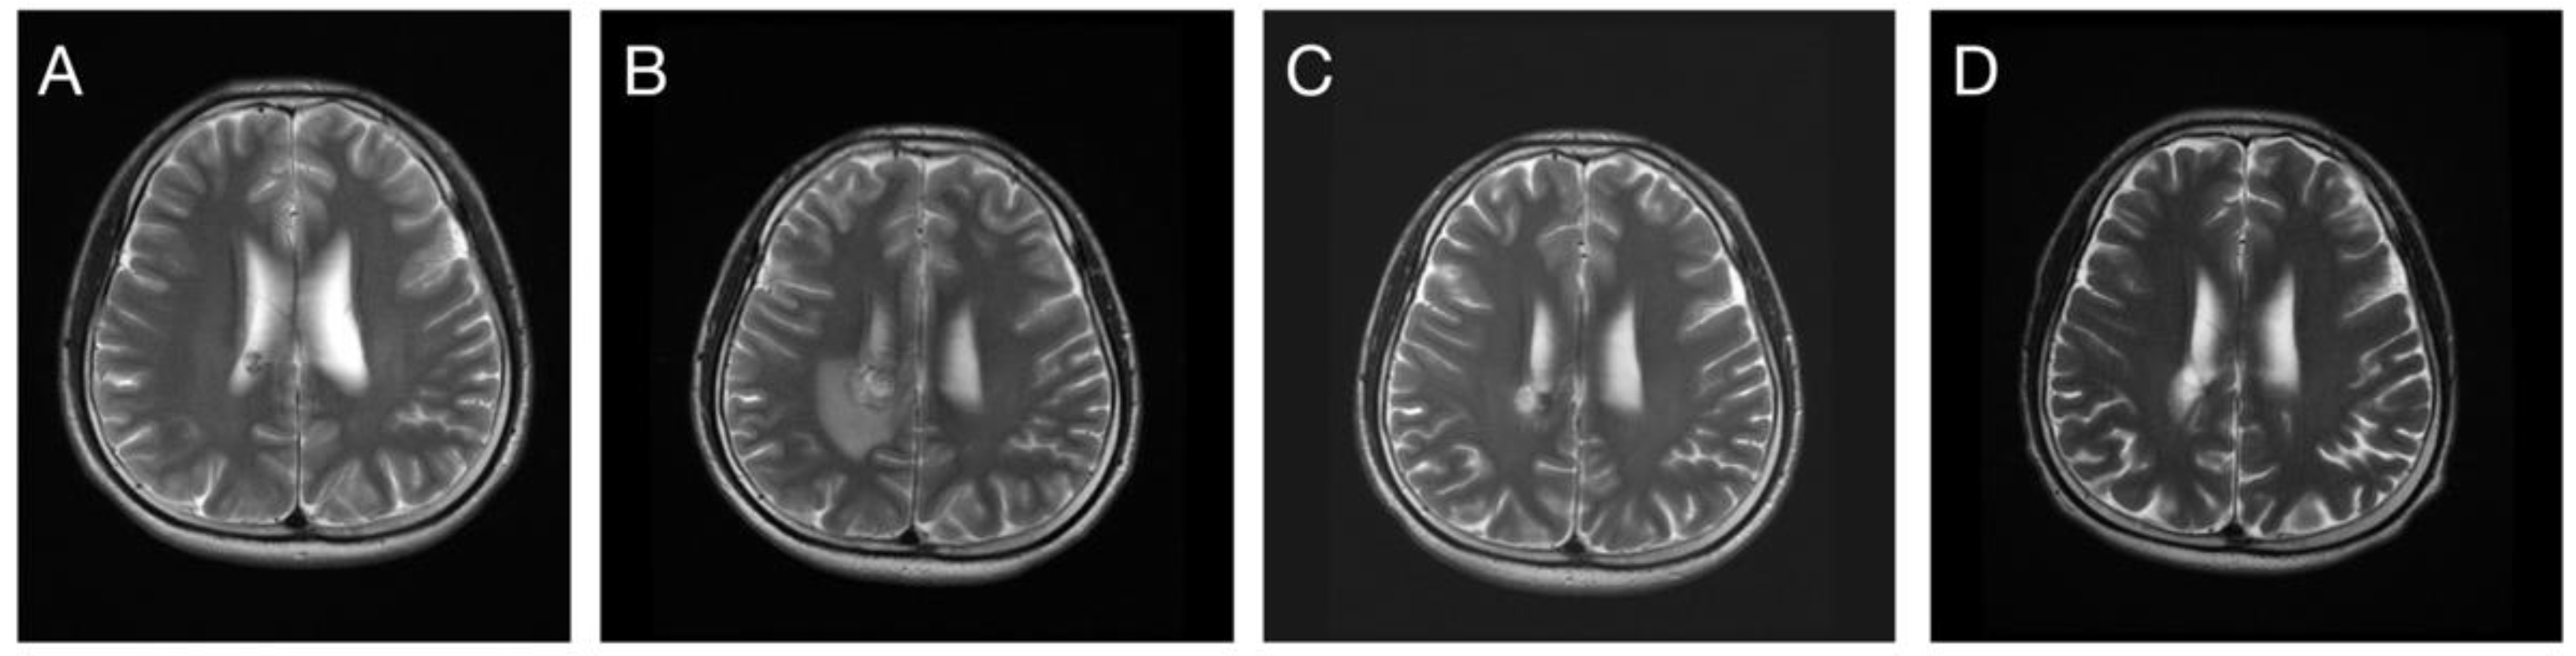

3.3. Response in Volume Control

3.4. Post-Radiosurgical Perifocal Brain Edema